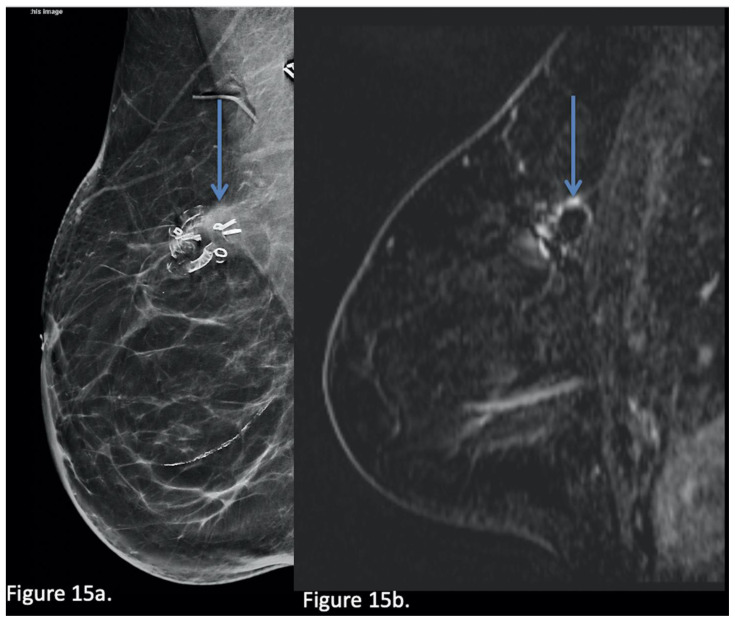

Figure 15.

63-year-old female with a BioZorb associated asymmetry.

Technique: Diagnostic Synthetic 2D mammogram MLO view obtained 3 years post op (a) (kVp: 31, mAs: 205) and subsequent Breast MRI (b) Sagittal post contrast T1-weighted subtracted sequence. Performed on a 3T magnet; 15 mL of gadoterate meglumine administered. TR 4, TE 1.44.

Findings: Concern of increased density (arrow in a) at the superior aspect of BioZorb site. This was then recommended for stereotactic biopsy, however the density was not seen on the day of the biopsy and MRI was recommended. MRI showed normal mild peripheral enhancement of surgical site (arrow in b) without evidence of suspicious mass or nodular enhancement to suggest recurrence.